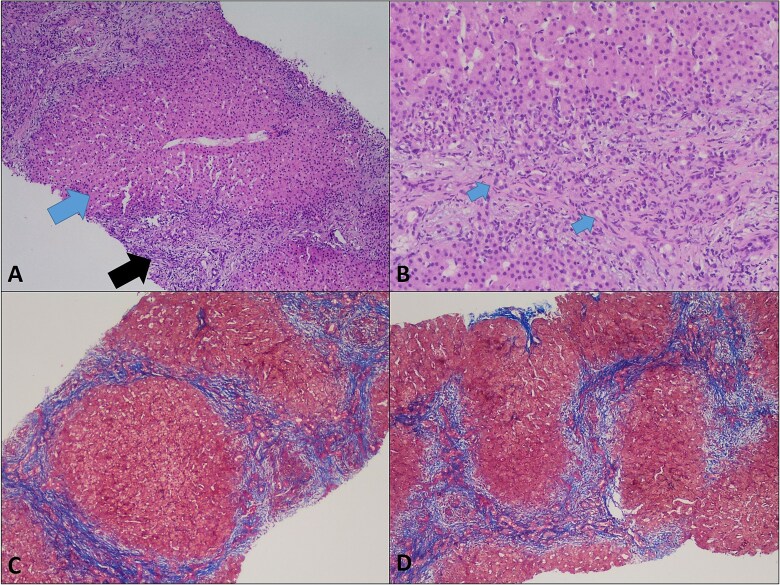

Sneddon syndrome (SS) is a rare neurocutaneous disorder consisting of livedo racemosa (LR) and cerebrovascular disease with an incidence of 4 per 1 000 000 annually. It may be idiopathic or associated with autoimmune or genetic factors, including deficiency of adenosine deaminase 2 (DADA2). We describe a 17-month-old girl with recurrent fevers, hepatosplenomegaly, LR, and progressive liver fibrosis. A pathogenic ADA2 mutation and LDLR mutation associated with familial hypercholesterolemia (FH) were detected by genetic testing. Despite corticosteroids, etanercept, and immunosuppressants, she continued to deteriorate and developed portal vein thrombosis and increasing hepatic dysfunction. DADA2 is well described to cause systemic vasculopathy, but its association with liver fibrosis is still unclear. Our case highlights a potential association between DADA2 and LDLR mutation leading to hepatic injury, extending the broad spectrum of SS-related complications. Further research is needed to understand the role of these genes and their mutations in the systemic and hepatic manifestations of SS.